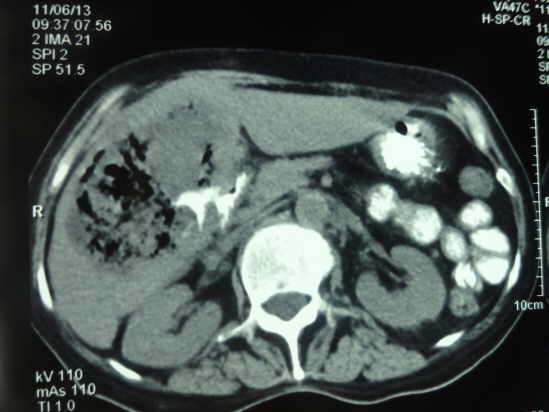

Tomografía Axial Computarizada de Absceso Hepático Amebiano

TAC abdominal con contraste es la técnica de elección para el diagnóstico de los abscesos hepáticos

La sintomatología del absceso hepático amibiano se ha englobado en lo que se denomina la “triada clásica”: hepatomegalia, dolor en hipocondrio derecho y fiebre, asociados a leucocitosis en presencia de neutrofilia y pruebas serológicas para E. histolytica positivas.